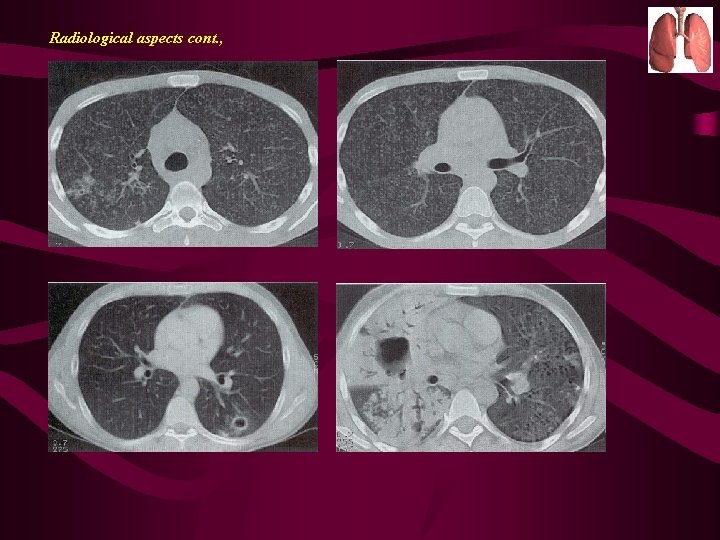

Diagnosis by X-ray: Chest x-rays: Multi nodular infiltrate above or behind the clavicle with or without pleural effusion unilaterally or bilaterally.

B) Radiography : Although X-rays are sensitive they are not specific Tuberculosis can mimic any disease on the X-ray.

Radiological aspects cont. ,